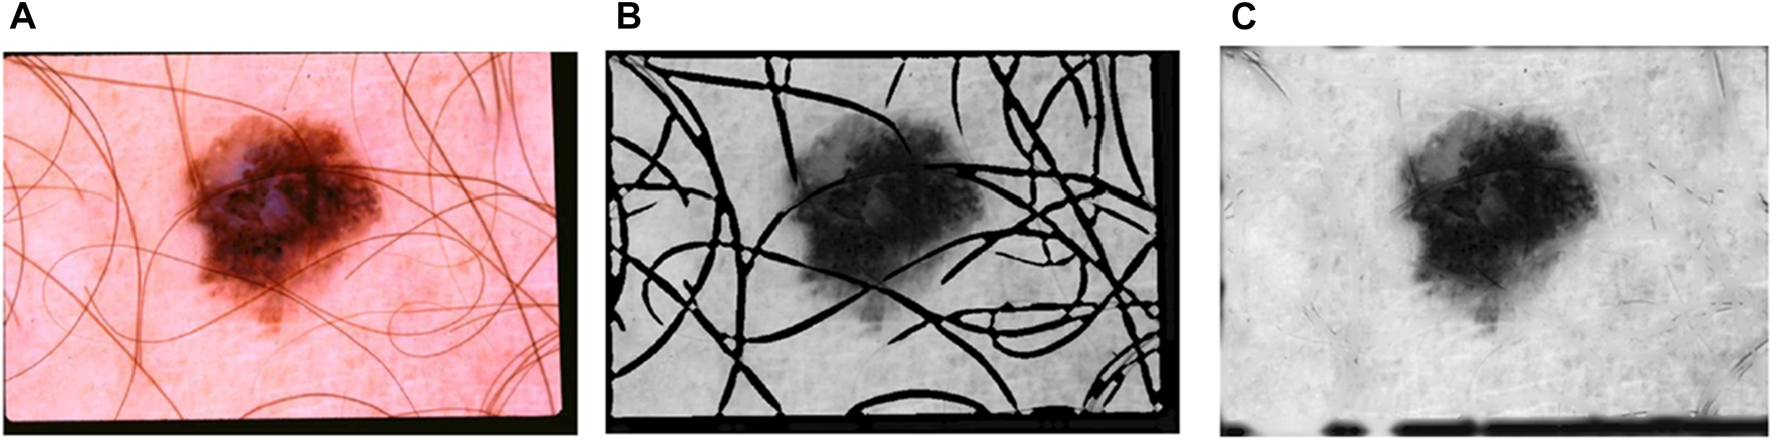

Cryotherapy can be administered using a cotton swab dipped in liquid nitrogen, a spray canister filled with the substance, or even a probe with liquid nitrogen running through it. These are only a few of the countless approaches available. Each of these strategies has its own set of advantages. Cryotherapy treatments can be administered using liquid nitrogen spray canisters in addition to traditional procedures. This strategy is just as effective as the others. The process takes less than a minute on average to complete. Automated melanoma detection consists of preprocessing, area extraction, postprocessing, and segmentation. Cleaning the data, integrating the data, reducing the data, and transforming the data are the four steps that comprise data preprocessing. These stages were created to make the process easier to manage. A digital image has been split. Non-lesion data is removed from images via image segmentation. Lesions’ shapes, sizes, skin types, and textures make segmentation difficult. Figure 1 shows images of malignant melanoma and benign dermoscopy; these artefacts may have an influence on feature computation and skin cancer classification. The lesion is separated after artefacts are removed. Following segmentation, we find and quantify melanoma subtypes.

FIGURE 1. Malignant and benign skin cancer images of the melanoma skin cancer dataset (Melanoma Skin Cancer, 2022).

FIGURE 4. (A) An image with hair (B) A black and white image (C) image after hair inpainting operation.